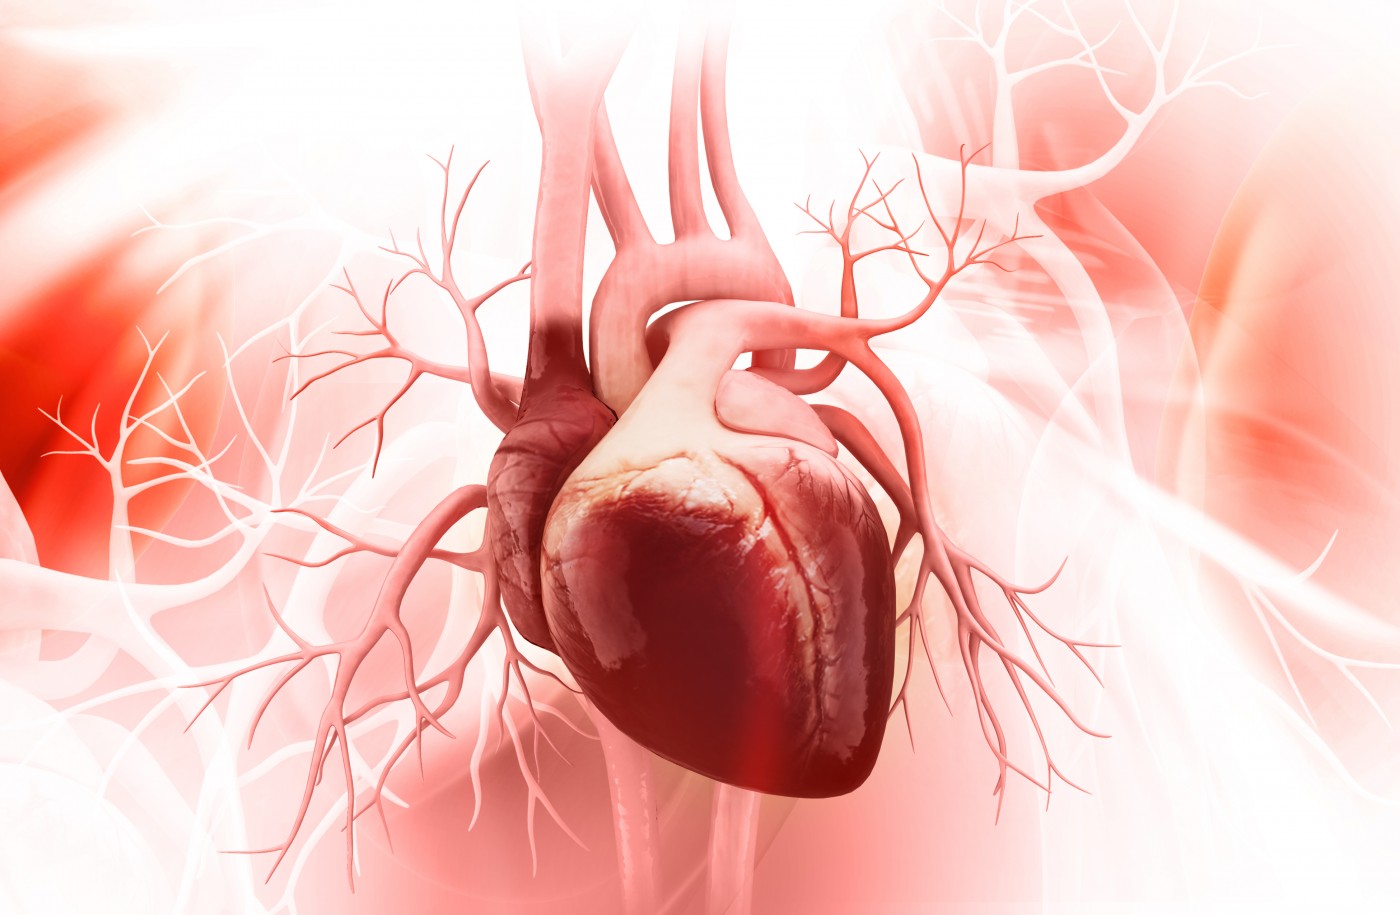

Анатомия здорового сердца: фотографии и иллюстрации